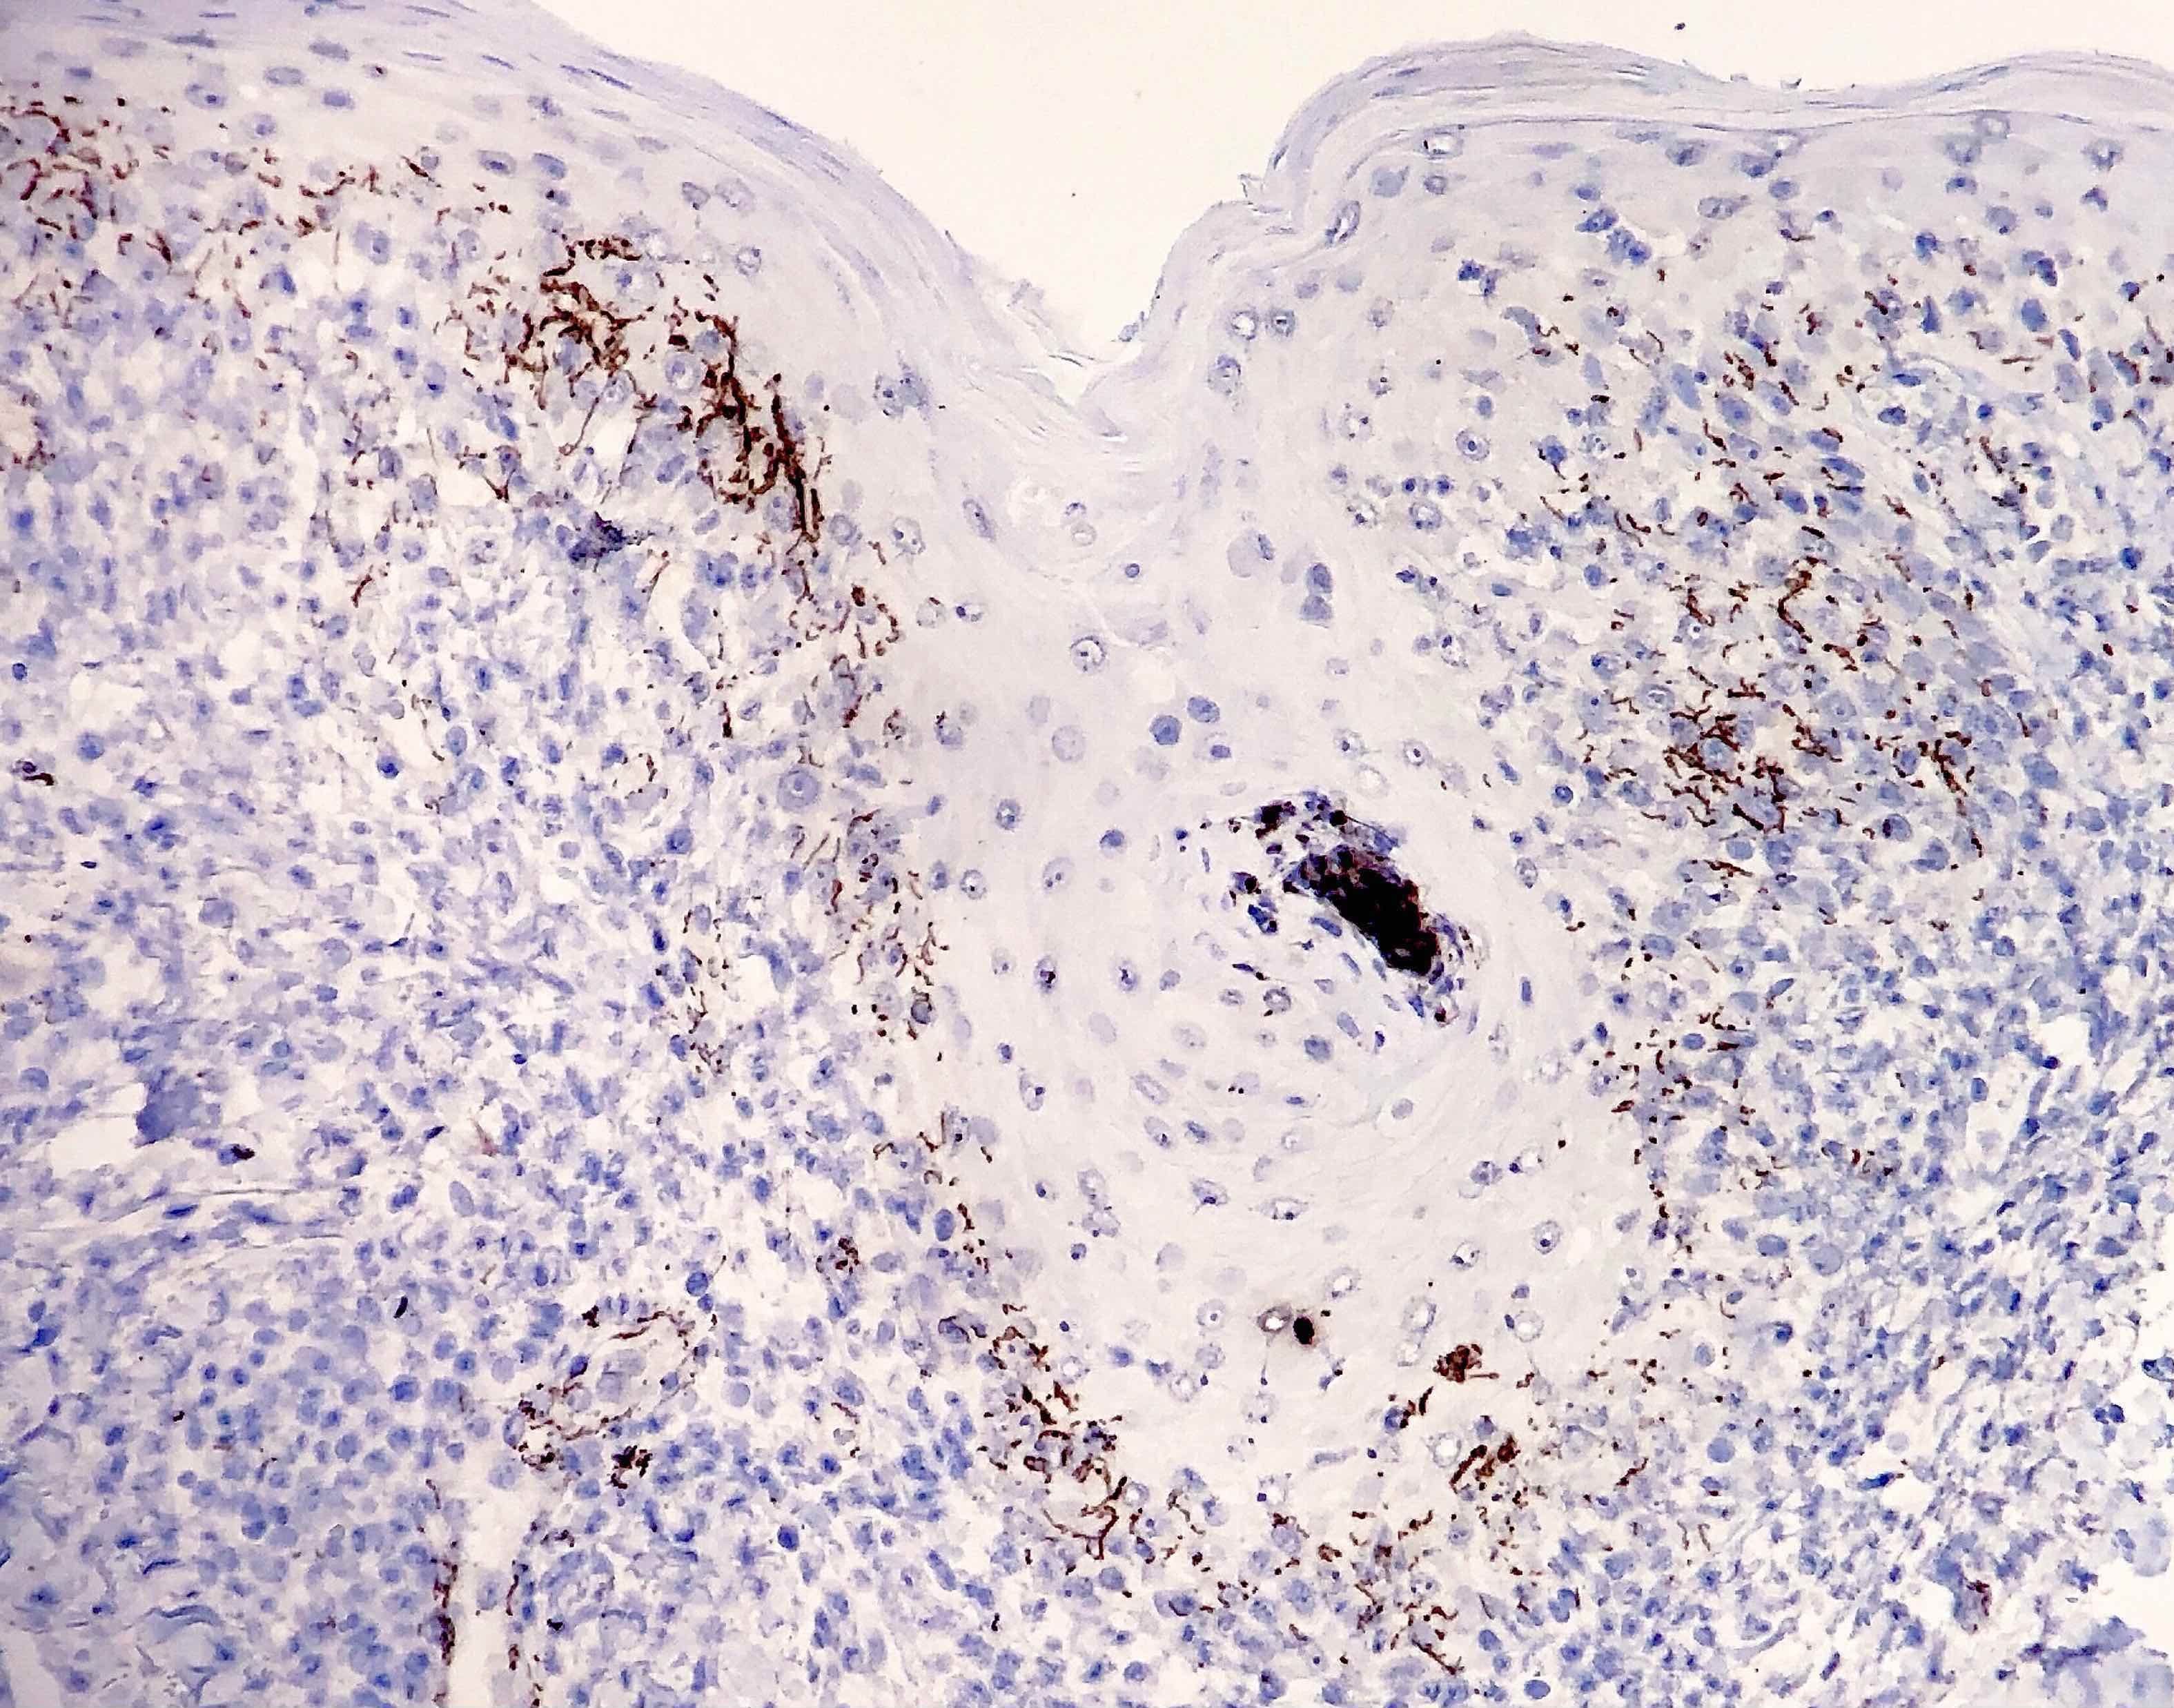

Microscopic (histologic) images

Contributed by Silvija P. Gottesman, M.D., Hillary Rose Elwood, M.D., Mark R. Wick, M.D. and AFIP images

- Immunohistochemical stain: treponema (71% sensitive) (J Cutan Pathol 2004;31:595)

- Skin, punch biopsy:

- Psoriasiform lymphohistiocytic inflammation with plasma cells (see comment)

- Comment: There is psoriasiform epidermal hyperplasia with superficial and deep perivascular lymphohistiocytic infiltrate. Admixed plasma cells are also noted. The infiltrate forms a band beneath the hyperplastic epidermis and envelopes some of the adnexal structures. Endothelial swelling of the superficial vascular plexus is present. A treponemal immunohistochemical stain shows numerous coiled spirochetes in the lower half of the epidermis. These findings are diagnostic of syphilis.